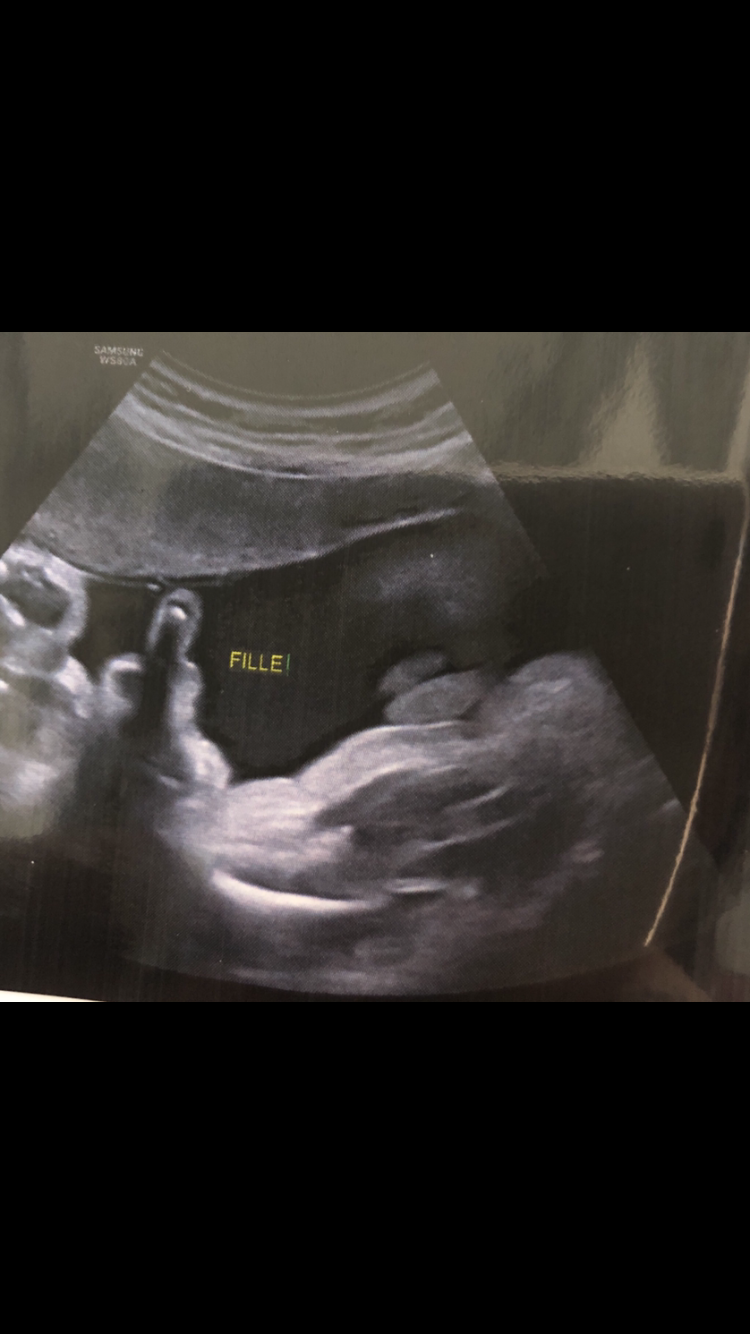

Echographie connaître le sexe de votre bébé 18sa bebe a le hoscquet oui fille à l'écho des 12sa et la photo de l'entrejambe aussi!Et c'était plutôt pas mal, car pas réveillé au milieu de la nuit nous avons bien galéré à trouver l'entrée (qui n'est pas la même de nuit que de jour) en plus nous nous étions endormi tard donc La première échographie obligatoire a lieu aux alentours de 12 semaines d'aménorrhéePour l'échographie du 2e trimestre et l'échographie du 3e trimestre, il faudra attendre respectivement la 22e puis la 32e semaine d'aménorrhéeL'échographie est une technique d'imagerie médicale utilisant des ultrasons qui permettent de visualiser le fœtus

Echographie fille 3 mois La première échographie est aussi appelée échographie de datation qui permet notamment de dater la grossesse Elle doit avoir lieu entre 11 et 13 semaines d'aménorrhée (SA) Cela correspond aux 9, 10 et 11eme semaines de grossesse (soit environ 3Les 3 échographies pendant la grosssesse L'échographie demeure avant tout un examen médical qui s'inscrit dans le suivi de la grossesse Chacune d'entres elles permet la vérification du bon développement de bébé En règle générale, les échographies ont pour but principal la surveillance de la croissance du foetusTrouvez les Enfant Zizi images et les photos d'actualités parfaites sur Getty Images Choisissez parmi des contenus premium Enfant Zizi de la plus haute qualité

La deuxième échographie, dite morphologique, s'effectue durant le 5ème mois de grossesse, entre la 18ème et la ème semaine Elle représente pour beaucoup de parents l'apogée des échographies avec la découverte du sexe du bébé !DR Ce qui n'est pas rassurant en voyant cette photo, c'est de se dire que le futur enfant risque de vous faire des concerts au milieu de la nuit après saCidessous, le classement des programmes pour lequels les subventions sont attribuées aux associations entre 10 et 18 Pour voir le détail et l'évolution année après année d'un programme particulier, cliquer sur l'un d'eux ou cliquez que "liste complète" pour contulter le reste des programmes Programme

Echographie comment savoir si c'est une fille ou un C'est aussi le mois de la fameuse échographie des 5 mois qui marque la deuxième rencontre avec bébé et pour tous les parents curieux, le grand moment va arriver fille ou garçon, le voile sera levé Calendrier de l'année 08Gros point positif à souligner Nous le savons, un enfant, ça coûte cher Mais deux, bonjour les trous dans le portefeuille vu qu'il faut tout acheter en double Sur La Boutique des Jumeaux, 1Bravo pour les somptueuses pages présentées "Lui" des Grenouillois 8 Lui

Prend soin de toi ma jolie et c'est tout mimi ce que vous achetez pour ce bb Gros bisous et repose toi au maximum Posté par Élodie, 11 ma A 17 SG on peut normalement te dire si ce sera une fille ou un garçon On a su la semaine dernière que ça serait un petit garçon, c'est que du bonheur! Découvrir le sexe de Bébé à l'échographie Les médecins peuvent vous dévoiler le sexe de votre bébé lors de la première échographie mais ils ne le révèlent généralement qu'à la deuxième car il existe une marge d'erreur au début Dessin du jour, vivement demain!

Echographie garçon ou fille 22 semaines est plusPsychologie durant la grossesse 3 pistes de lectures essentielles et 100% bienêtre pour les futures mamans Pour le papa aussi la grossesse est un changement Établir un lien avec bébé dès le début de la grossesseÉchographie garçon puis fille A l'échographie du premier trimestre, le professionnel observe le bourgeon génitalC'est son orientation qui renseigne sur le sexe de l'enfant , détaille le Dr Mironneau En effet, si à l'écran, le bourgeon génital a une orientation verticale alors le bébé à naître est certainement un garçon Ainsi de nombreux échographes attendent l'échographie du